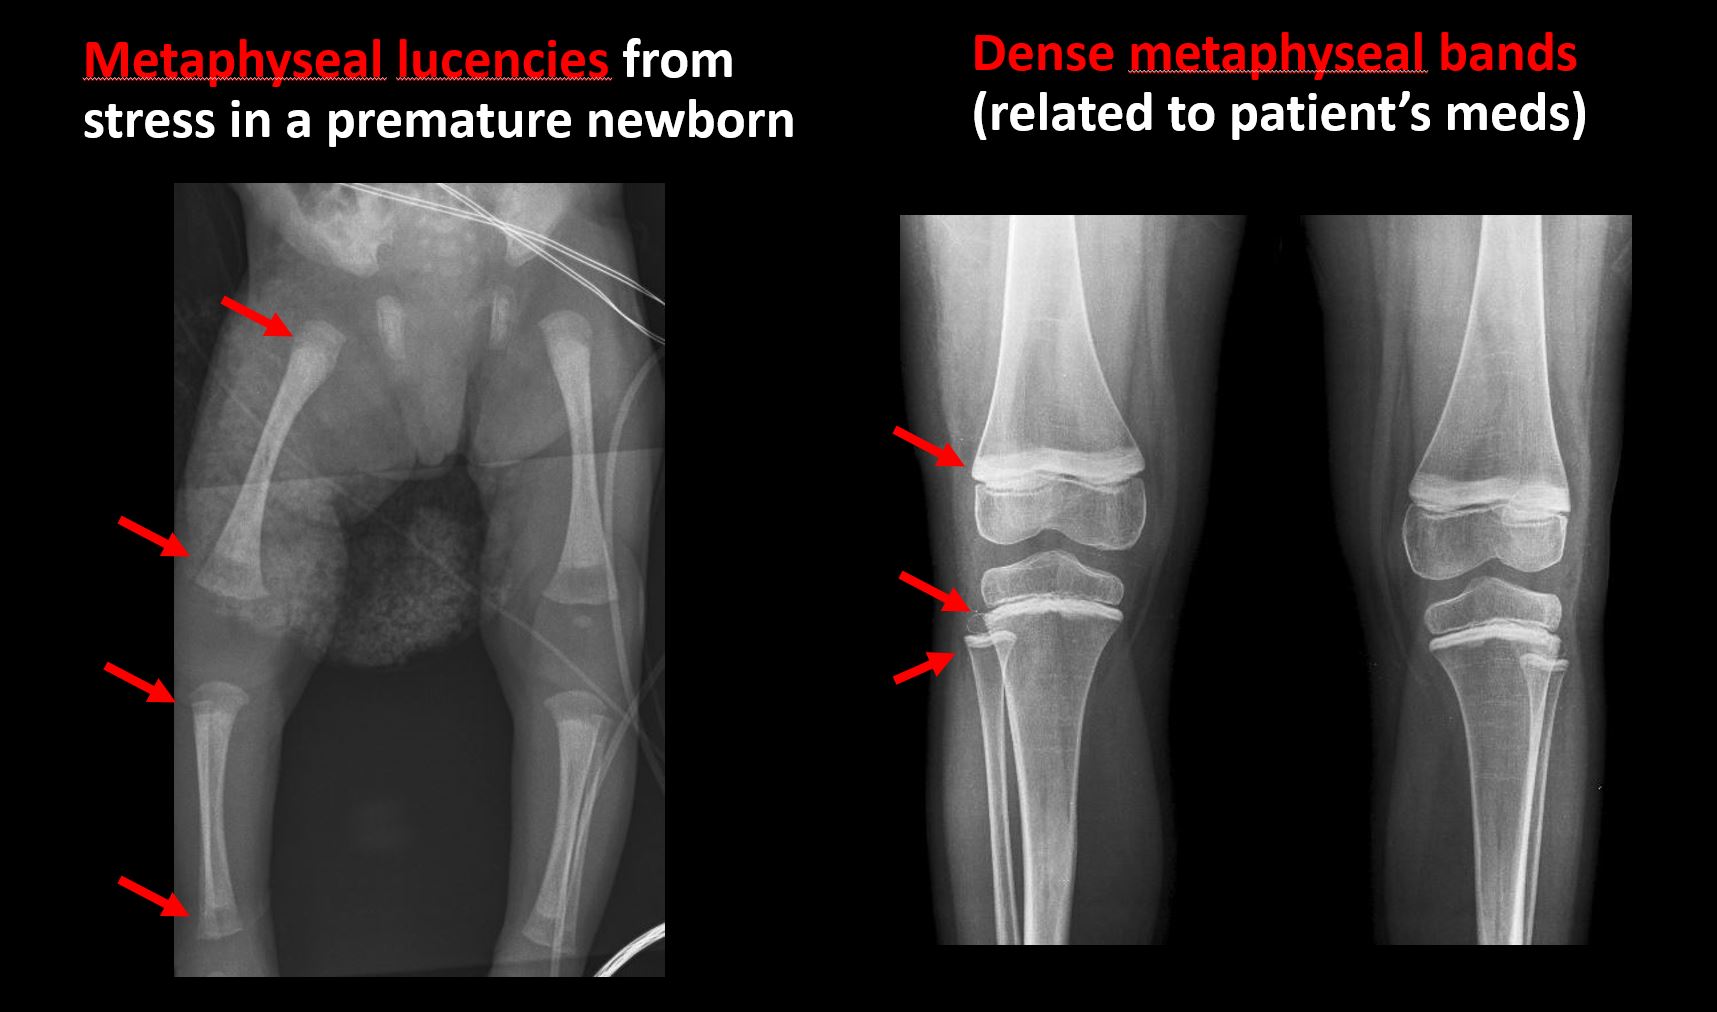

There is metaphyseal abnormality (lucencies, increased density, erosion) which may be from something other than injury such as stress, metabolic disease (e.g. rickets), neoplasm (e.g. leukemia), heavy metals, inflammation, or infection. [Yes/No]